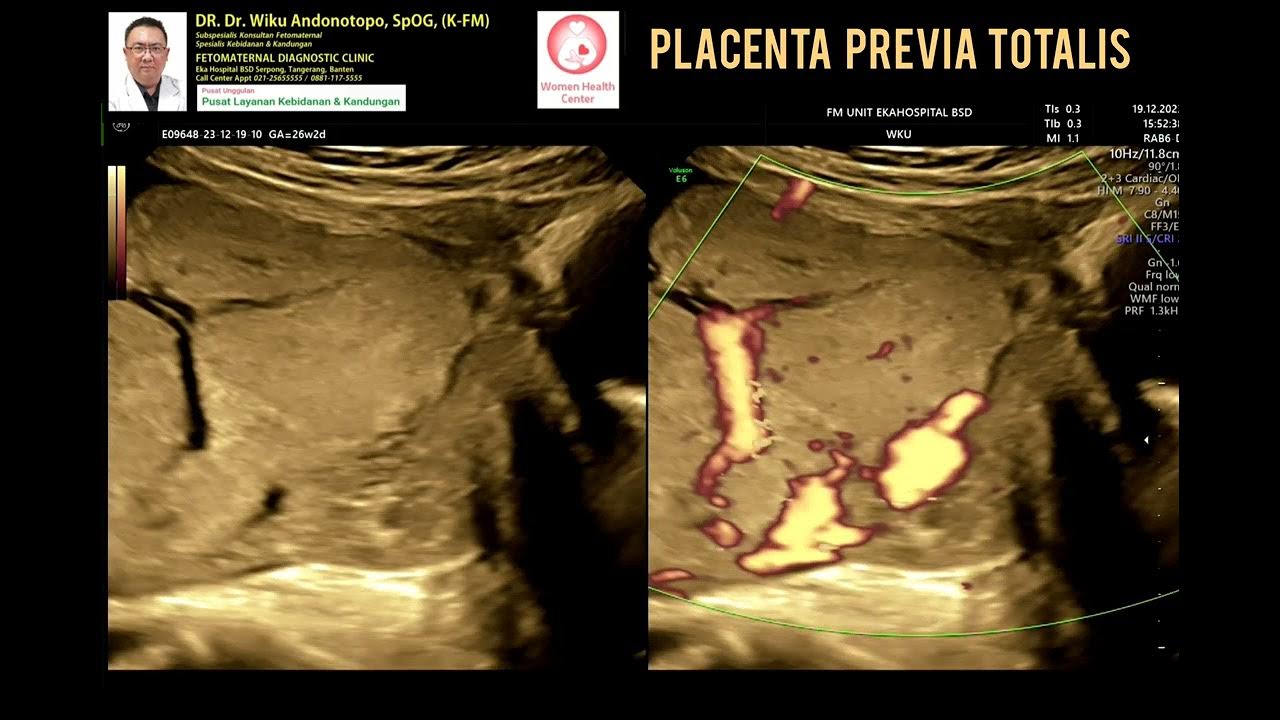

Was ist Placenta praevia totalis? Bei der „ Placenta praevia totalis " (lateinisch: im Weg liegende Plazenta) liegt die Plazenta direkt vor der Muttermundöffnung, somit ist der Geburtskanal verlegt und eine Spontangeburt unmöglich. In diesem Artikel werden wir uns eingehend mit dieser Erkrankung befassen, ihre Ursachen, Symptome, Diagnose und Behandlungsmöglichkeiten beleuchten

Eine Plazenta praevia liegt am Muttermund und führt oft zu Blutungen in der Schwangerschaft Die häufigste Ursache für eine dystope Insertion der Plazenta ist eine vorausgegangene Schädigung des Endometriums Die Plazenta Praevia Totalis ist eine ernstzunehmende Komplikation während der Schwangerschaft, die eine sichere Entbindung erschwert

PlazentaPathologien ELearning mit Lecturio. Eine Plazenta praevia liegt am Muttermund und führt oft zu Blutungen in der Schwangerschaft Ultraschall Es entsteht der Verdacht auf eine Placenta praevia bei schwangeren Frauen mit Scheidenblutungen, die während des zweiten oder dritten Schwangerschaftstrimesters einsetzen